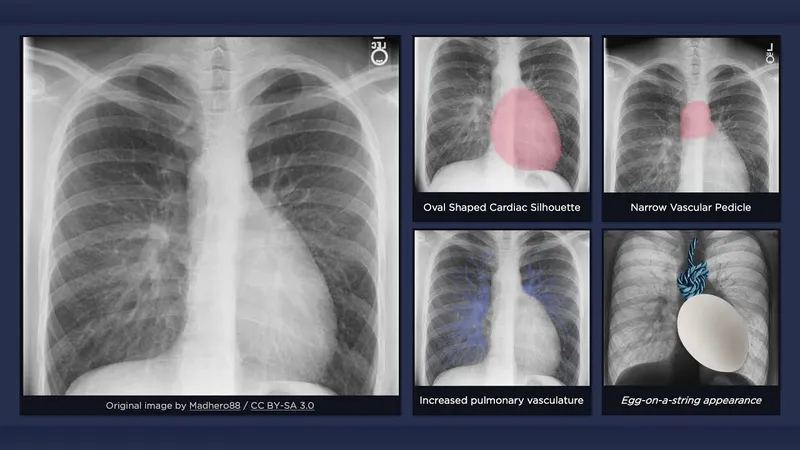

| CXR | Boot-shaped | Egg-on-string |

Boot-shaped

Egg-on-string